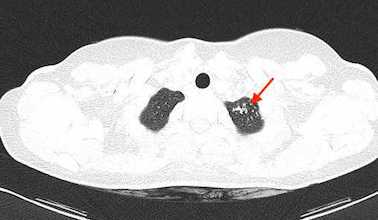

Gli esami ematochimici in corso di ricovero sono risultati nella norma, comprese le sierologie per le principali infezioni e i marcatori tumorali (salvo aumento di CA-125, 445 UI/ml); il Quantiferon è risultato positivo. Agli esami strumentali Rx torace negativa, mentre la TC torace evidenziava adenopatie mediastiniche e noduli polmonari apicali a sinistra (Figura 1); alla TC e RM addome multiple adenopatie e abbondante liquido ascitico (Figura 2), risultato poi negativo per bacillo di Koch (BK) su esame batterioscopico, colturale e analisi molecolare.